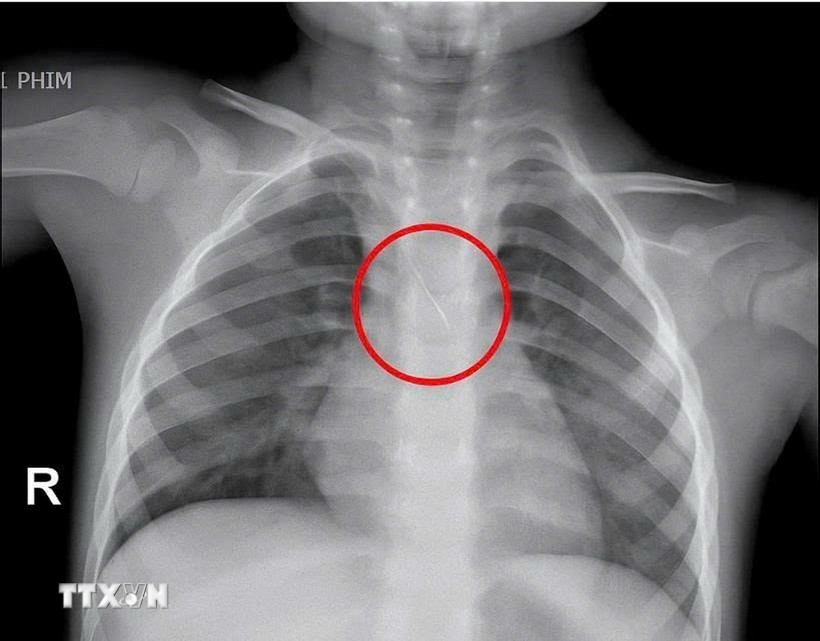

Hình ảnh chiếc kim chọc tủy rơi vào trong đường thở của bé trai 3 tuổi. (Ảnh: TTXVN phát)

Kết quả chụp phim cho thấy, một dị vật kim loại dài khoảng 22mm nằm ở góc carina (vị trí chia đôi khí quản) đe dọa gây tắc nghẽn đường thở của trẻ.

Dị vật được phát hiện có một đầu nhọn cắm vào 1/3 dưới khí quản, đầu còn lại nằm trong phế quản gốc trái, được xác định rất nguy hiểm.